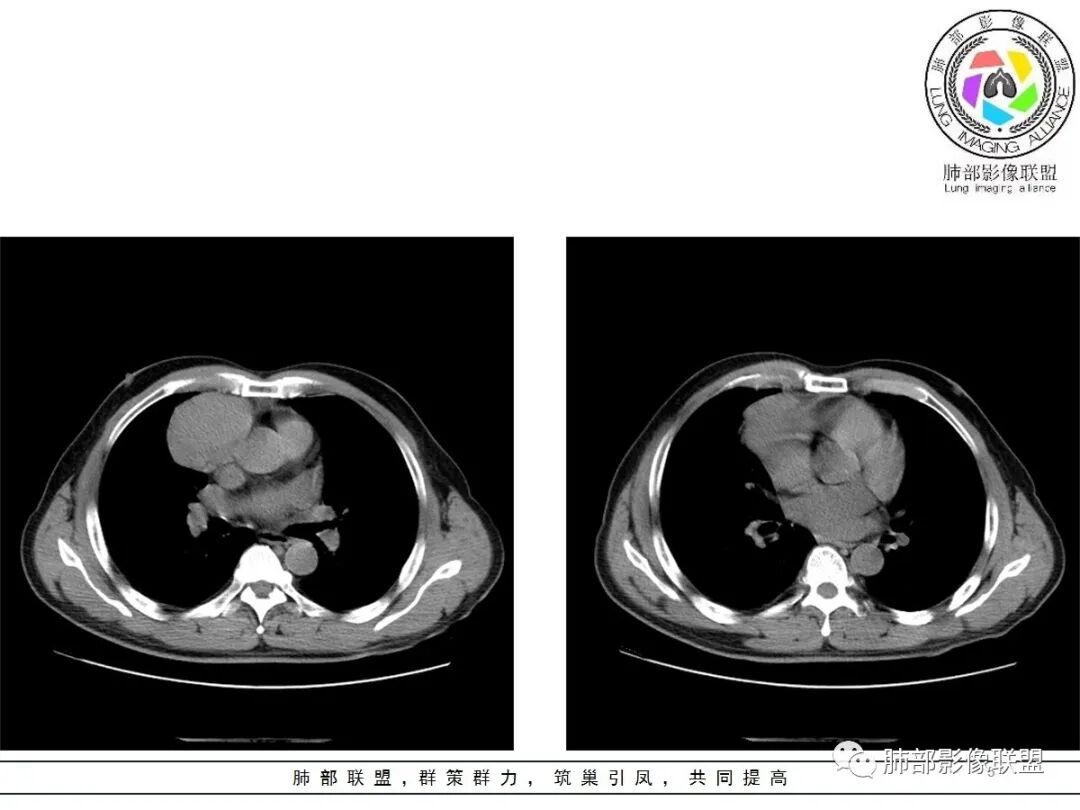

小赵:这个是3月15日的视频

小赵:第二个是3月19日的视频

大雄:老年男性  急性起病 胸痛1天前纵隔占位伴右侧少量胸水,肿块整体膨隆,密度不均匀,可见坏死,纵隔脂肪间隙模糊不清常规考虑胸腺瘤/癌并梗死

一切∮随缘:定位肺外,病变位于右前纵隔,与肺部交接面清晰,有胸膜尾征,心包局部受压,部分包绕主动脉血管,平扫密度均匀,形态规则,膨胀性生长,增强扫描壁有强化,内容物无明显强化,考虑1:淋巴瘤2:胸腺瘤3:神经鞘瘤4:支气管囊肿

亚东:前纵隔囊实性肿物,形态尚规则 ,与心包分界不清,内可见小气泡,嚢内平扫密度低,强化不明显,囊壁强化,右胸腔积液,淋巴结肿大不明显,化验白细胞高,支持囊肿伴感染。

小强:前纵隔肿块,边缘模糊,其内有点状气体影,环形强化(肉芽肿?),心包胸膜受累,疾病谱:胸腺瘤(一般是侵袭性胸腺瘤累计心包,胸膜,强化不符合)淋巴瘤,生殖细胞瘤(年龄,AFP不高不负),考虑畸胎瘤,囊性畸胎瘤合并感染,边缘模糊,累计心包胸膜,3.19病变进展,胸腔积液,可能有破溃

采莲:老年男性,胸疼病史,右上前纵隔肿块,边缘光滑,平扫内部密度稍均匀,轻度强化,内有低密度区,与支气管关系不大,右侧少量积液。考虑来源纵隔,老年男性,胸腺瘤或胸腺癌,鉴别淋巴瘤。

周围脂肪间隙密度增高,内部小点状很低密度影

右侧少量胸水

19日,4天后, 内部低密度影有,周围渗出增多,胸水增多

薄膜状强化

影像上周围病灶变化明显

常规肿瘤侵犯不支持,太快

应该是炎性病变渗出

脂肪密度明显,还有钙化、囊性病变,支持含脂质类病变破裂

周围是化学性炎症或出血所致

后期强化,可能与炎症有关

可能:1、肿瘤或瘤样病变破裂出血或内部物质外溢所致2、炎性病变所致

对比一下:

肿瘤样病变破裂所致纵隔炎应该没错

南边:肿瘤或肿瘤样病变破裂所致纵隔炎,这是大方向

2.胸膜掀起,右侧内乳动脉略增粗,定位右前上纵隔内占位。

3.右上纵隔囊实性占位,边界清楚。中央见点状脂肪密度影,边缘见一点状钙化影,增强不均匀环形强化。

4.四天内病灶变化快,块影增大且不规则,包膜似不完整,边界不清,上份可见浸润或渗出,与周围心脏大血管及心包等间隙不清。胸水增多。

5.未见明显淋巴结增大

第一次的检查符合胸腺瘤影像学改变,短期内的形态学改变及突然出现的边界模糊或浸润等,符合出血或炎症。